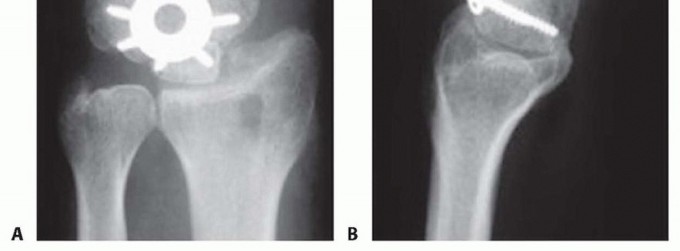

TECH FIG 2 • A,B. AP and lateral radiographs showing a circular plate fusion construct. On the lateral view, the plate is nicely seated to prevent dorsal impingement.